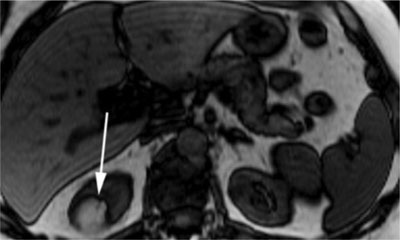

More recently, the application of MRI artefacts has been suggested to evaluate fat in renal tumours. One of them, the chemical shift artefact, is due to the differences between resonance frequencies of fat and water. This results in alternating high and low signals in the frequency encoding direction on opposed-phase imaging. This out-of-phase cancellation effect between fat and water gives rise to another MRI artefact, called the black boundary or India ink artefact. This artificially created black line is located at the junction of fat (present in AML cells) and water (present in renal parenchyma) and results in a sharp delineation of the muscle-fat boundary (Figure 5). This sign is indicative of an AML [341116]. It is especially useful in fat-poor AMLs and very small lesions, in which the typical T1 features may not be noticeable [2]. However, fat-invisible AMLs do not show this decrease in signal intensity, because they contain too little fat cells [10].

Figure 5

Opposed-phase T1-weighted MR image with a hyperintense renal mass. The India ink artefact (arrow) is present at the interface of the lesion with the kidney [16].